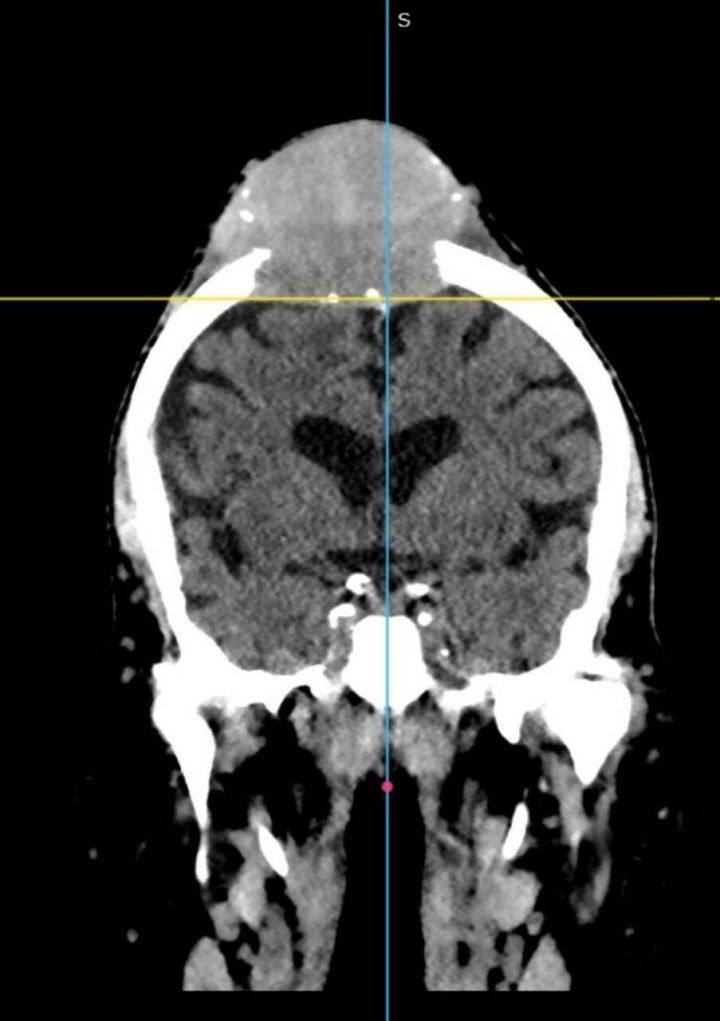

11 ноября в Республиканскую клиническую больницу Татарстана поступил 78-летний мужчина с постоянно растущим образованием на голове.

Образование, по словам врачей, начало увеличиваться несколько месяцев назад и стало причиной серьезного беспокойства у пациента и его семьи. После первичного осмотра и ряда анализов, медики решили провести дополнительные исследования, чтобы выяснить природу образования.

Врачи отметили, что подобные случаи не являются редкостью, однако важно провести диагностику как можно скорее, чтобы исключить серьезные заболевания. В ходе обследования пациента будут использоваться различные методы, включая МРТ и биопсию.